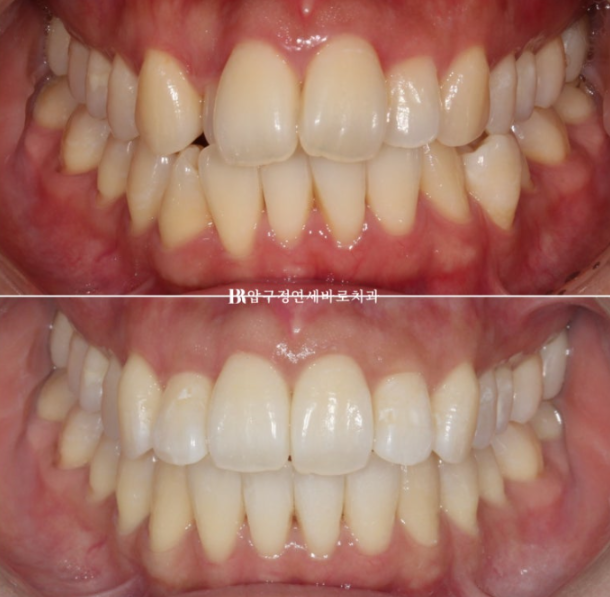

24.02~24.08

오늘은 앞니 반대교합 등이 있는 복잡한 케이스에서 앞니 부분교정으로 어떻게 치료하는 지 보여드리겠습니다.

지난 2월, 예비신부님 앞니 부분교정을 위해 찾아왔습니다.

24.02

측절치 덧니가 아랫니와 거꾸로 물리는 반대교합을 보입니다.

2달 간 마무리 교정 후 치료시작 6개월 만에 치료를 마무리 했습니다.

24.08

정확히 맞아 떨어지는 중심선

거꾸로 물리는 덧니는 해결이 되었고

작은 어금니까지 배열을 마쳤습니다.

마치 전체교정 한 것과 같은 효과를 목표로 치료에 임합니다.

앞니 부분교정은 치료기간도 짧고 간단해보이지만 전체교정을 한 것과 같은 효과를 얻기는 쉽지 않습니다.

내려와 토끼이처럼 보이던 앞니는 높이가 맞아졌고 기울어짐도 치축개선을 통해 좋아졌습니다.

걸려있던 앞니도 제 위치를 찾았습니다.